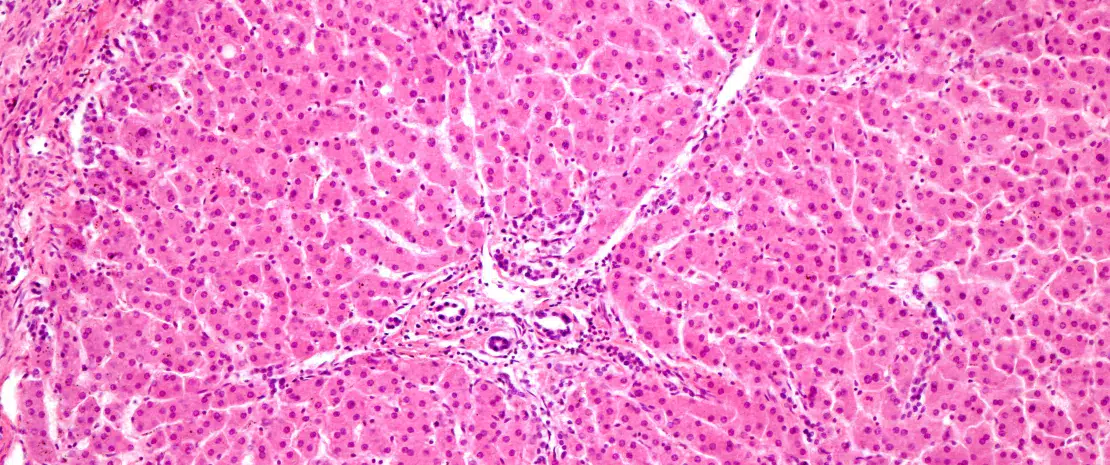

Des dysbioses intestinales et une augmentation des marqueurs inflammatoires ont déjà été retrouvées chez les alcooliques chroniques, notamment en cas de TUA sévères et de besoins compulsifs à boire. Elles entraîneraient une neuroinflammation engendrant des troubles cognitifs et comportementaux, notamment sociaux.

Or des déficits de cognition sociale ont été rapportés chez des jeunes « binge drinkers ». Ces dysbioses et ces perturbations de l’axe intestin-cerveau pourraient ainsi être impliquées dans le passage vers une addiction à l’alcool.

Des dysbioses associées au binge-drinking et à des troubles cognitifs

Les chercheurs ont observé que le « binge drinking » s’accompagnait de déséquilibres taxonomiques et fonctionnels particuliers du microbiote intestinal, eux-mêmes associés à des troubles de la gestion émotionnelle. Les analyses statistiques ont montré que l’altération de la reconnaissance des émotions était liée à une diminution d’espèces de Clostridium, de Flavonifractor plautii et de Eggerthella lenta et à une augmentation des Coprococcus. L’impulsivité était associée à une baisse des Collinsella et à une hausse des Roseburia et des Parabacteroides. Les besoins compulsifs d’alcools étaient également corrélés à une réduction de Ruthenibacterium lactiformans et à une libération accrue d’interleukines, signe de surstimulation immunitaire. Enfin, un plus grand nombre d’épisodes de « binge drinking » était associé à une baisse de production de l’acide gras à chaîne courte isovalérate et à une plus grande impulsivité.